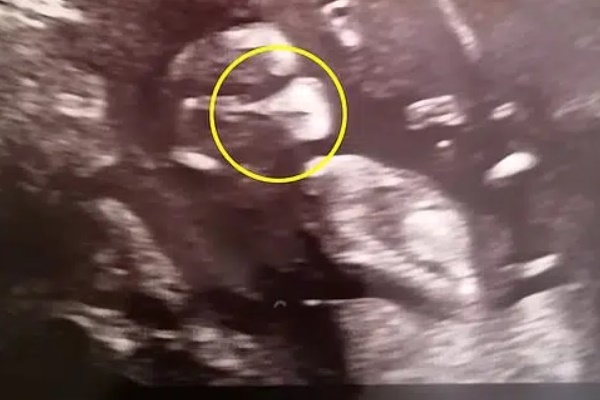

Vợ chồng chị Sarah Beeston, đến từ Hawaii (Mỹ), cũng giống như vậy. Họ luôn mong chờ đến từng kỳ siêu âm để được xem hình hài của con. Song, họ đã vô cùng thất vọng khi nghe bác sĩ nói rằng em bé không có tóc vì trên hình ảnh siêu âm hoàn toàn không nhìn thấy một sợi tóc nào, dù vợ chồng chị Sarah ai cũng có mái tóc dày vàng óng.

Tuy nhiên, tóc có thể mọc như "um tùm" cỏ dại, nhưng cũng có thể chúng chỉ mọc một chút vào cuối thai kỳ. Điều này có nghĩa là không phải lúc nào bác sĩ siêu âm cũng nhìn thấy chính xác bộ tóc của trẻ.